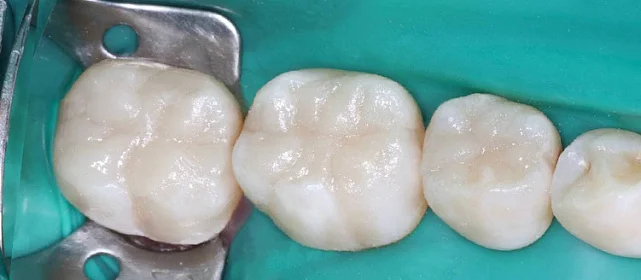

Зубы выровнены, смыкание нормализовано. Установлены несъёмные ретейнеры на обе челюсти. Пациент направлен к ортопеду.

Решение: Поставили элайнеры Invisalign на обе челюсти. Лечение заняло 4 года — случай потребовал нескольких этапов коррекции, каждый из которых последовательно приближал зубы к нужному положению. Капы менялись каждые 1–2 недели, контрольные визиты — для отслеживания прогресса и выдачи новых наборов. Зубы встали на место, смыкание пришло в норму. Зафиксировали ретейнеры на обе челюсти, пациент направлен к ортопеду для завершающего этапа.

Случай потребовал нескольких последовательных этапов коррекции. Invisalign позволяет дозаказывать капы в рамках лечения, и здесь это понадобилось — каждый следующий этап доводил положение зубов точнее. Результат достигнут, прикус стабилен, ретейнеры на месте. Пациента направила к ортопеду.